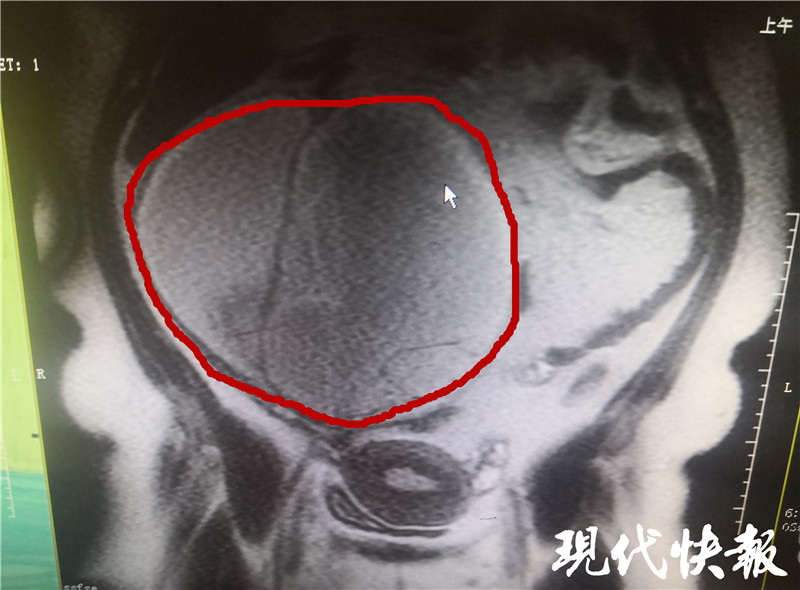

(通訊員 李雨純 劉威 記者 李子璇)近日,淮安吳女士(化姓)發(fā)現(xiàn)下腹隱隱作痛,該女子體重達(dá)到260斤,在醫(yī)院進(jìn)一步檢查后發(fā)現(xiàn),她盆腔有一個(gè)巨大包塊,直徑超過了25厘米,比一個(gè)西瓜還大,占據(jù)了整個(gè)盆腔。

△直徑超25cm

吳女士的情況比較特殊,由于體型肥胖,盡管囊腫已經(jīng)大到占滿盆腔,但還是被肚皮掩蓋,此時(shí)囊腫直徑已經(jīng)超過25厘米。